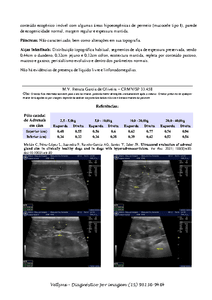

A Manu está com câncer na bexiga. Atualmente o câncer está num tamanho que ocupa quase toda a bexiga. Ela mal dorme pois precisa levantar toda hora para fazer xixi, e quando faz, sai sangue.

Eu gastei tudo o que podia para levar ao veterinário, fazer os exames e conseguir o diagnóstico de câncer, além da medicação para a dor, que ela tem bastante. Agora preciso de ajuda para custear a cirurgia de remoção do câncer e o tratamento posterior, além de despesas com transporte, caso venham a surgir.